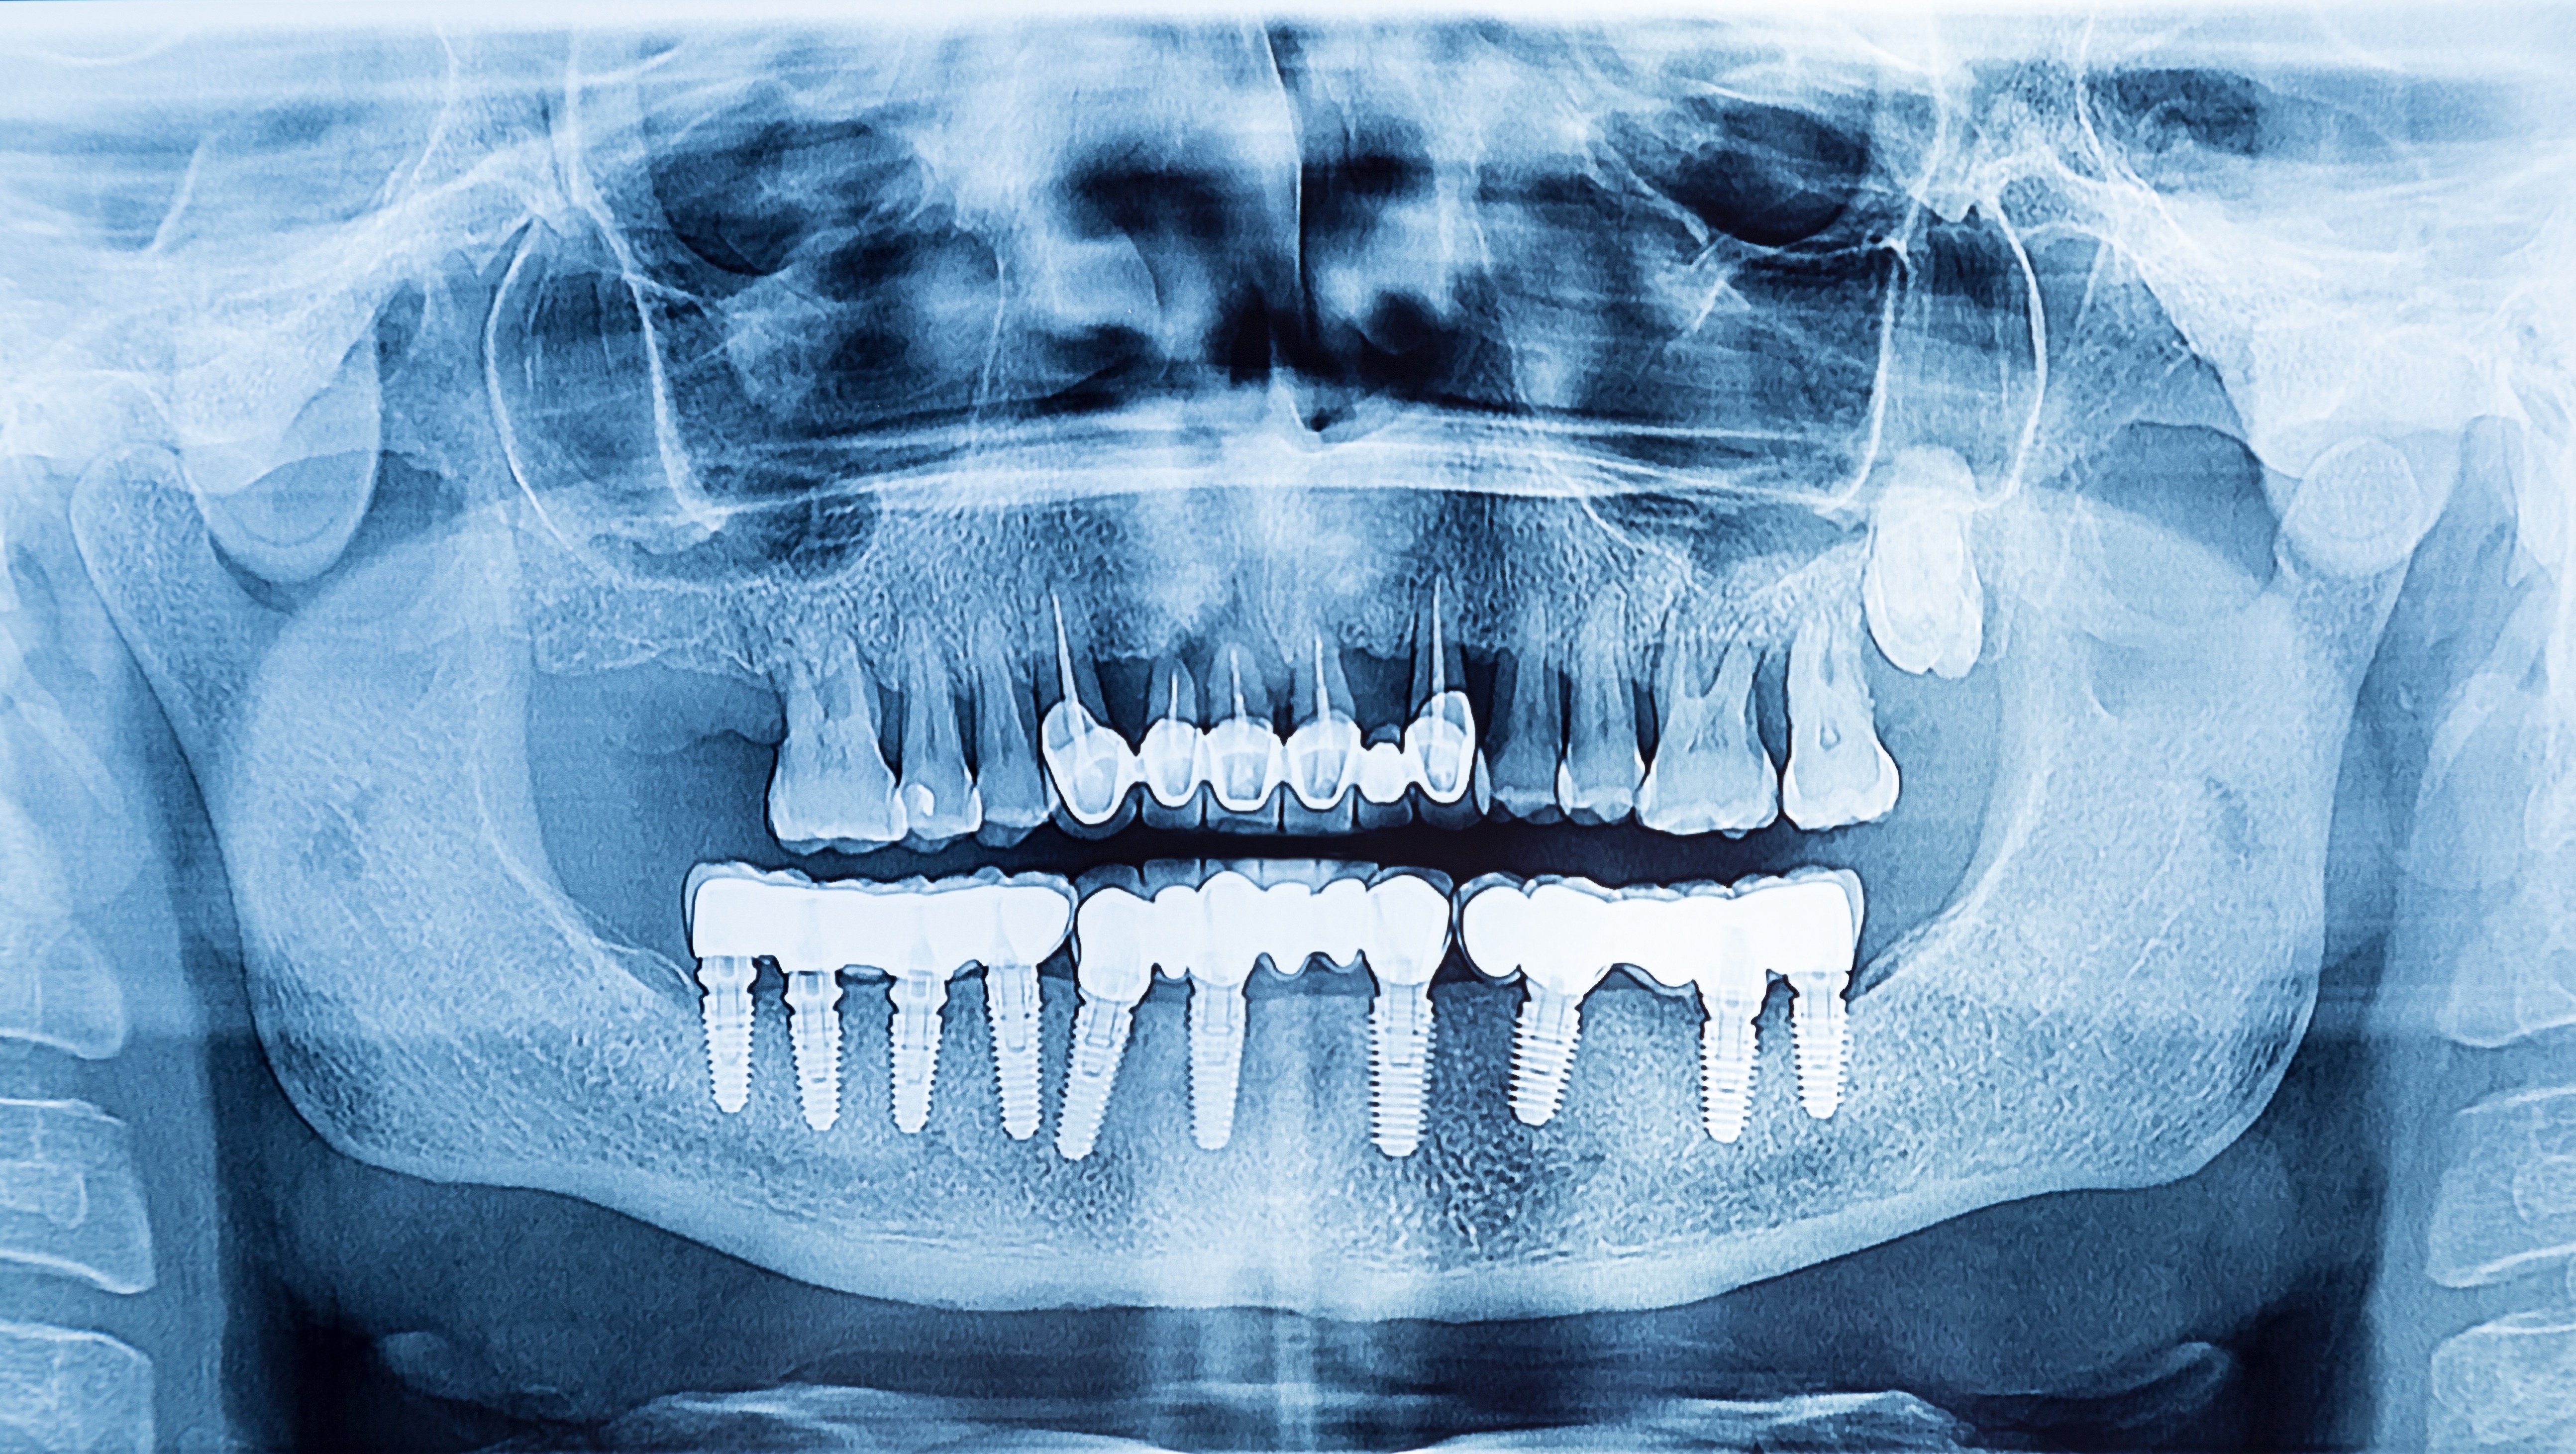

Um peri-implantäre Erkrankungen korrekt diagnostizieren zu können, ist es hilfreich gute und aussagekräftige Röntgenbilder zu haben. Jedoch können gerade peri-apikale Kleinbildröntgen von Implantaten oft „verschwommen“ geraten. Es gibt aber eine sehr einfache Regel, um diese Bilder zu korrigieren und die Implantatwindungen exakt und scharf abzubilden und dadurch das Knochenniveau exakt bestimmen zu können! Diese Regel ist darüber hinaus einfach zu merken und vor allem im klinischen Alltag schnell umzusetzen:

Was bedeutet das nun? Unabhängig davon ob ein Röntgenbild von einem Implantat im 1./4. oder 2./3. Quadranten angefertigt wird, wenn sich die rechte Seite des Implantates am Röntgenbild unscharf darstellt, muss der Strahlengang angehoben werden; das heißt man „zielt“ mehr nach oben, um die rechte Seite des Implantates schärfer abzubilden. Stellt sich aber die linke Seite des Implantates unscharf dar, muss man den Strahlengang senken, das heißt man „zielt“ mehr nach unten, um die linke Seite des Implantates schärfer abzubilden.